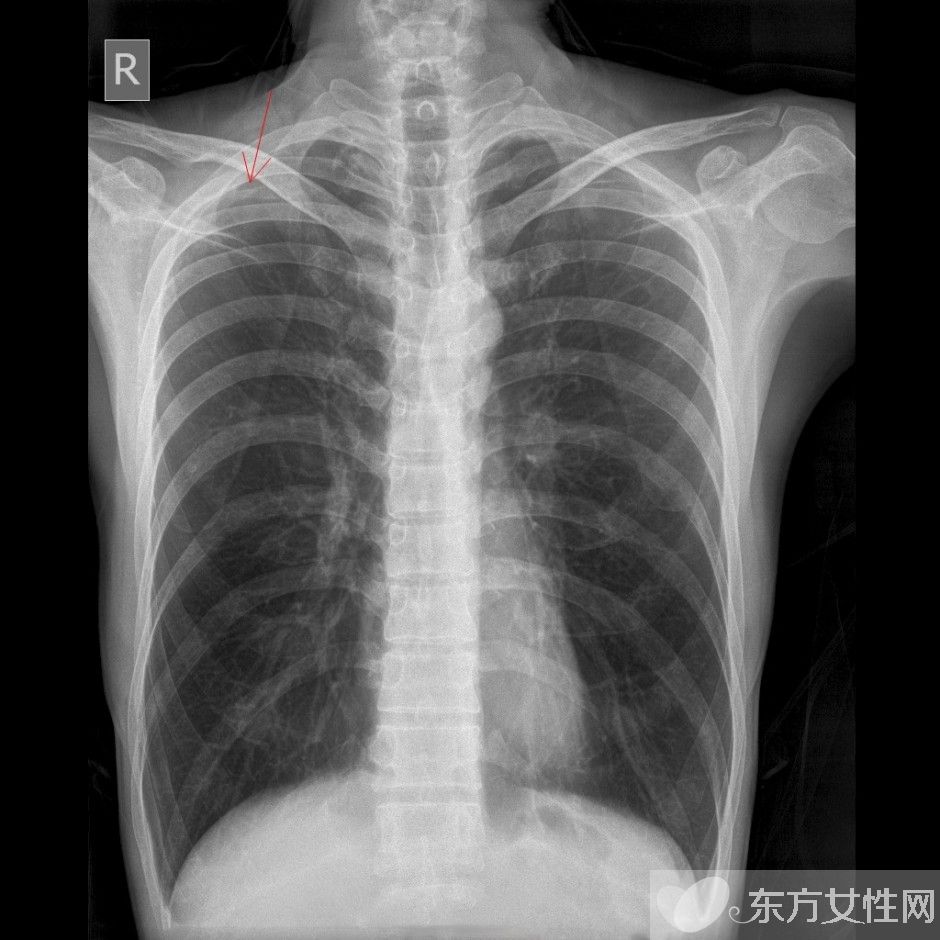

肺氣腫是指終末細(xì)支氣管遠(yuǎn)端(呼吸細(xì)支氣管,肺泡管、肺泡囊和肺泡)的氣道彈性減退,過度膨脹,充氣和肺容積增大或同時(shí)伴有氣道壁破壞的病理狀態(tài)。按其發(fā)病原因肺氣腫有如下幾種類型:老年性肺氣腫,代償性肺氣腫,間質(zhì)性肺氣腫,灶性肺氣腫,旁間隔性肺氣腫,阻塞性肺氣腫。